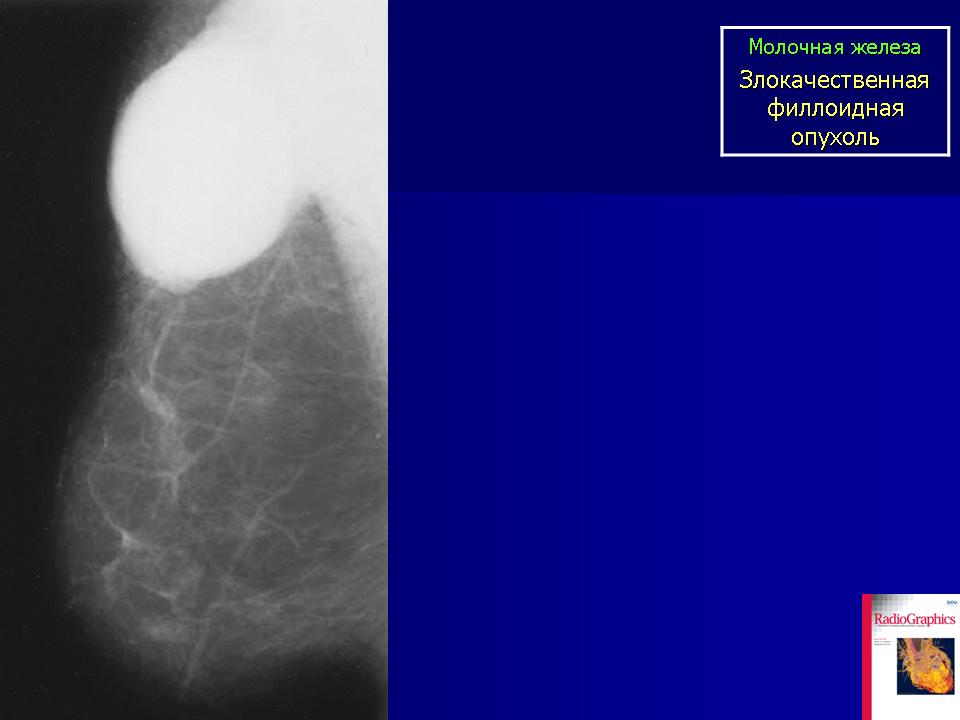

Фото 1. Фиброаденому на ранней стадии может распознать только врач после аппаратной диагностики